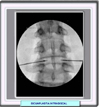

Bajo control radioscópico se introducen en el anillo fibroso del disco protuído, los introductores de los terminales de radiofrecuencia. Estos últimos cuentan en su extremo con un sensor de temperatura distal, que monitoriza la temperatura ofrecida por el electrodo y otro sensor proximal que mide la temperatura del disco en su periferia. Ambos sensores aportan información a una unidad de enfriamiento, que consiste en una bomba peristáltica de agua que envía el flujo necesario de líquido para evitar el sobrecalentamiento del disco, a través de una tubería que se continúa en el interior del electrodo y permite tener una temperatura constante en la punta del mismo, evitando de esa manera daño innecesario al disco.

La colocación de los electrodos debe ser en la zona de transición del anillo con el núcleo pulposo en posición posterior y posterolateral. Luego de generada la radiofrecuencia se provocará en el disco una deshidratación del núcleo y un acortamiento de las fibras del anillo, lo que provocará una retracción del mismo y dando lugar en el foramen a la desaparición de la compresión de la raíz emergente.